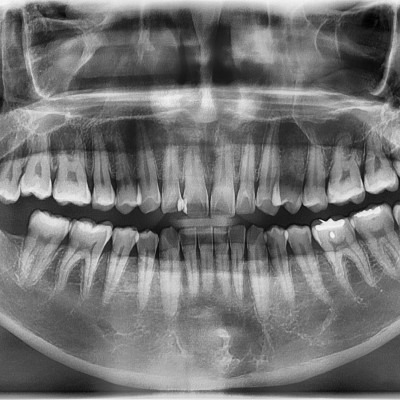

#18,28,38,48 사랑니 발치 N새글 #18,28,38,48 사랑니 발치 구강 외과 전문의가 당일 발치했습니다. --------------------..